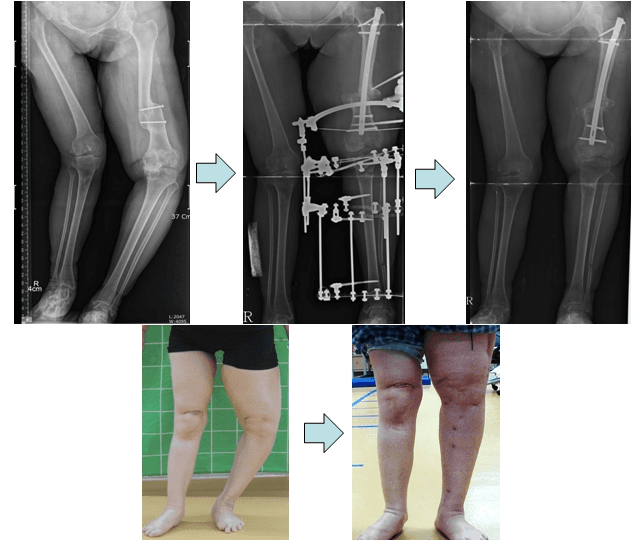

무릎관절손상후 발생한 하지변형에서의 교정